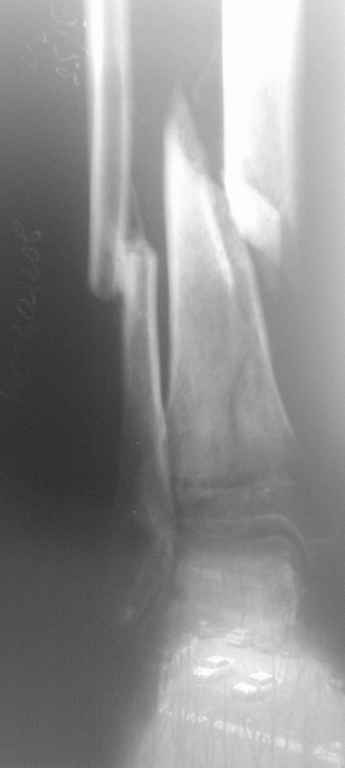

Д\з Неправильно консолидированный перелом м\берцовой кости, ложный сустав(учитывая подвижность в области перелома) б\берцовой кости правой голени. Остеопороз костей правой голени, стопы. Постиммобиллизационные контрактуры коленного, голеностопного суставов.

Больной Б. травма в августе месяце 2010г., находился на СВ, отказался от оперативного лечения со слов больного не имел средств на приобретение металлоконструкций, СВ вытяжение демонтировано ч\з 3 недели, была наложена циркулярная гипсовая повязка от кончиков пальцев стопы до с\3 бедра ,снят 10 ноября, имеется Rg контроль по снятию повязки,   первичных и после демонтажа СВ  снимков  не предоставил, почему не продолжил лечение на СВ нет сведений.

Сейчас кожные покровы правой голени отёчны, пастозны, умеренно гиперемированны, движения в коленном суставе  сгибание 90гр., разгибание 165, голеностопном в пределах качательных. Определяется подвижность в месте перелома. Осевая нагрузка болезненна.

На консилиуме решено (учитывая отсутствие возможности наложения аппарата Илизарова) выполнить остеотомию м\берцовой кости остеопериостальную декортикацию б\берцовой кости,репозиция(возможно с укорочением) фиксацию отломков кортикальными винтами, циркляжом  с последующим наложением циркулярной гипсовой повязки. Почему не было выполнено при первом поступлении или не доведена репозиция на СВ для меня вопрос.